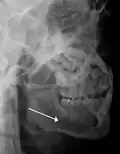

Plain film radiography

Traditionally, plain films of the mandible would be exposed but had lower sensitivity and specificity owing to overlap of structures. Views included AP (for parasymphsis), lateral oblique (body, ramus, angle, coronoid process) and Towne's (condyle) views. Condylar fractures can be especially difficult to identify, depending on the direction of condylar displacement or dislocation so multiple views of it are usually examined with two views at perpendicular angles.[11]

Towne's view of a bilateral condyle fracture. White arrow is a fracture on the neck of the condyle. Black arrow shows the condyle pulled to the medial. The same injury can be seen on the opposite side -